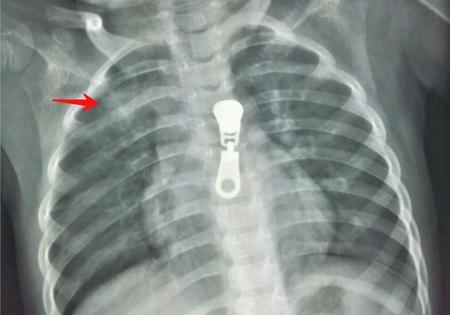

2.小儿胸片 这是诊断小儿肺炎的首选检查。3岁以上儿童尽量立位拍摄,缩短曝光时间减少运动伪影。

这是一位四岁女童,右上支原体肺炎。